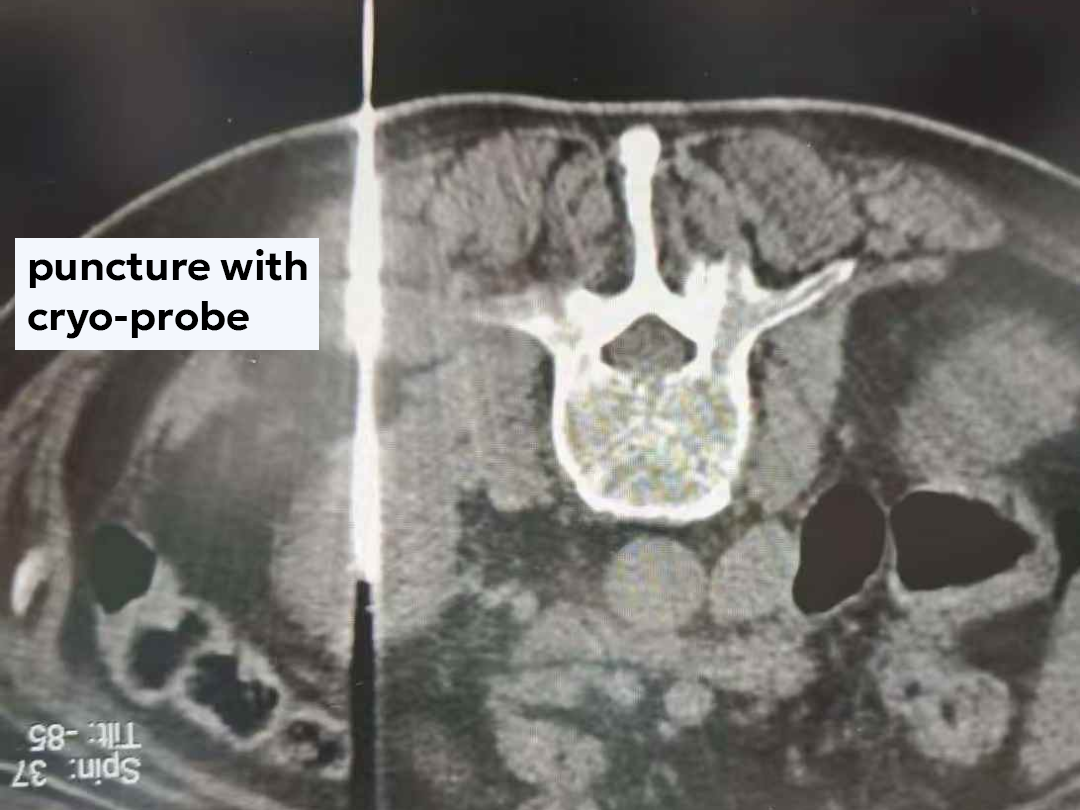

Taking into account the family’s strong wishes and Mr. Li’s physical condition, the team ultimately devised a personalized treatment plan:

cryoablation followed by targeted therapy.

Cryoablation destroys tumor cells by freezing them at ultra-low temperatures. With minimal trauma and rapid recovery, it is especially suitable for elderly patients with multiple comorbidities.

“We did the cryoablation on November 18, he was transferred from the ICU to a general ward on the 19th, and after the urinary catheter was removed on the 20th, he was already wandering around like a little kid, happily chatting with other patients,” Mr. Li’s daughter told us with a smile.